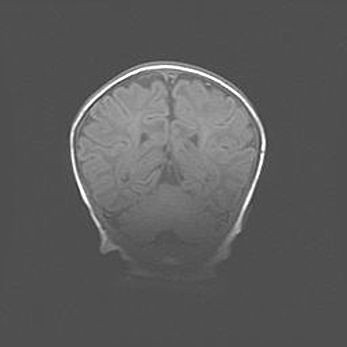

Наружная гидроцефалия с возможной атрофией височных областей.

Возраст: 28 дней

Вес: 3670 г

Пол: мужской

Окружность головы: 38 см

Срок гестации: 40 недель

Гидроцефалия головного мозга у новорожденных – это заболевание, которое характеризуется скоплением избыточного количества спинномозговой жидкости в желудочковой системе головного мозга в результате затруднения её перемещения от места выработки к месту поглощения в кровеносную систему или вследствие нарушения абсорбции. При открытой наружной форме гидроцефалии у новорожденных расширяются и переполняются субарахноидные пространства.

При нормотензивных  формах,  которые,  как  правило,  являются  следствием  перенесенных ишемических  повреждений  паренхимы  мозга,  возможно  сочетание микроцефалии  с нормотензивной гидроцефалией. В основе данных изменений лежит атрофия больших полушарий с преимущественной  локализацией  в  лобно-височных  областях.